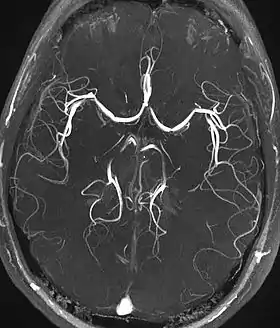

Magnetic resonance angiography

Magnetic resonance angiography (MRA) generates pictures of the arteries to evaluate them for stenosis (abnormal narrowing) or aneurysms (vessel wall dilatations, at risk of rupture). MRA is often used to evaluate the arteries of the neck and brain, the thoracic and abdominal aorta, the renal arteries, and the legs (called a "run-off"). A variety of techniques can be used to generate the pictures, such as administration of a paramagnetic contrast agent (gadolinium) or using a technique known as "flow-related enhancement" (e.g., 2D and 3D time-of-flight sequences), where most of the signal on an image is due to blood that recently moved into that plane (see also FLASH MRI).[35]

Techniques involving phase accumulation (known as phase contrast angiography) can also be used to generate flow velocity maps easily and accurately. Magnetic resonance venography (MRV) is a similar procedure that is used to image veins. In this method, the tissue is now excited inferiorly, while the signal is gathered in the plane immediately superior to the excitation plane—thus imaging the venous blood that recently moved from the excited plane.[36]